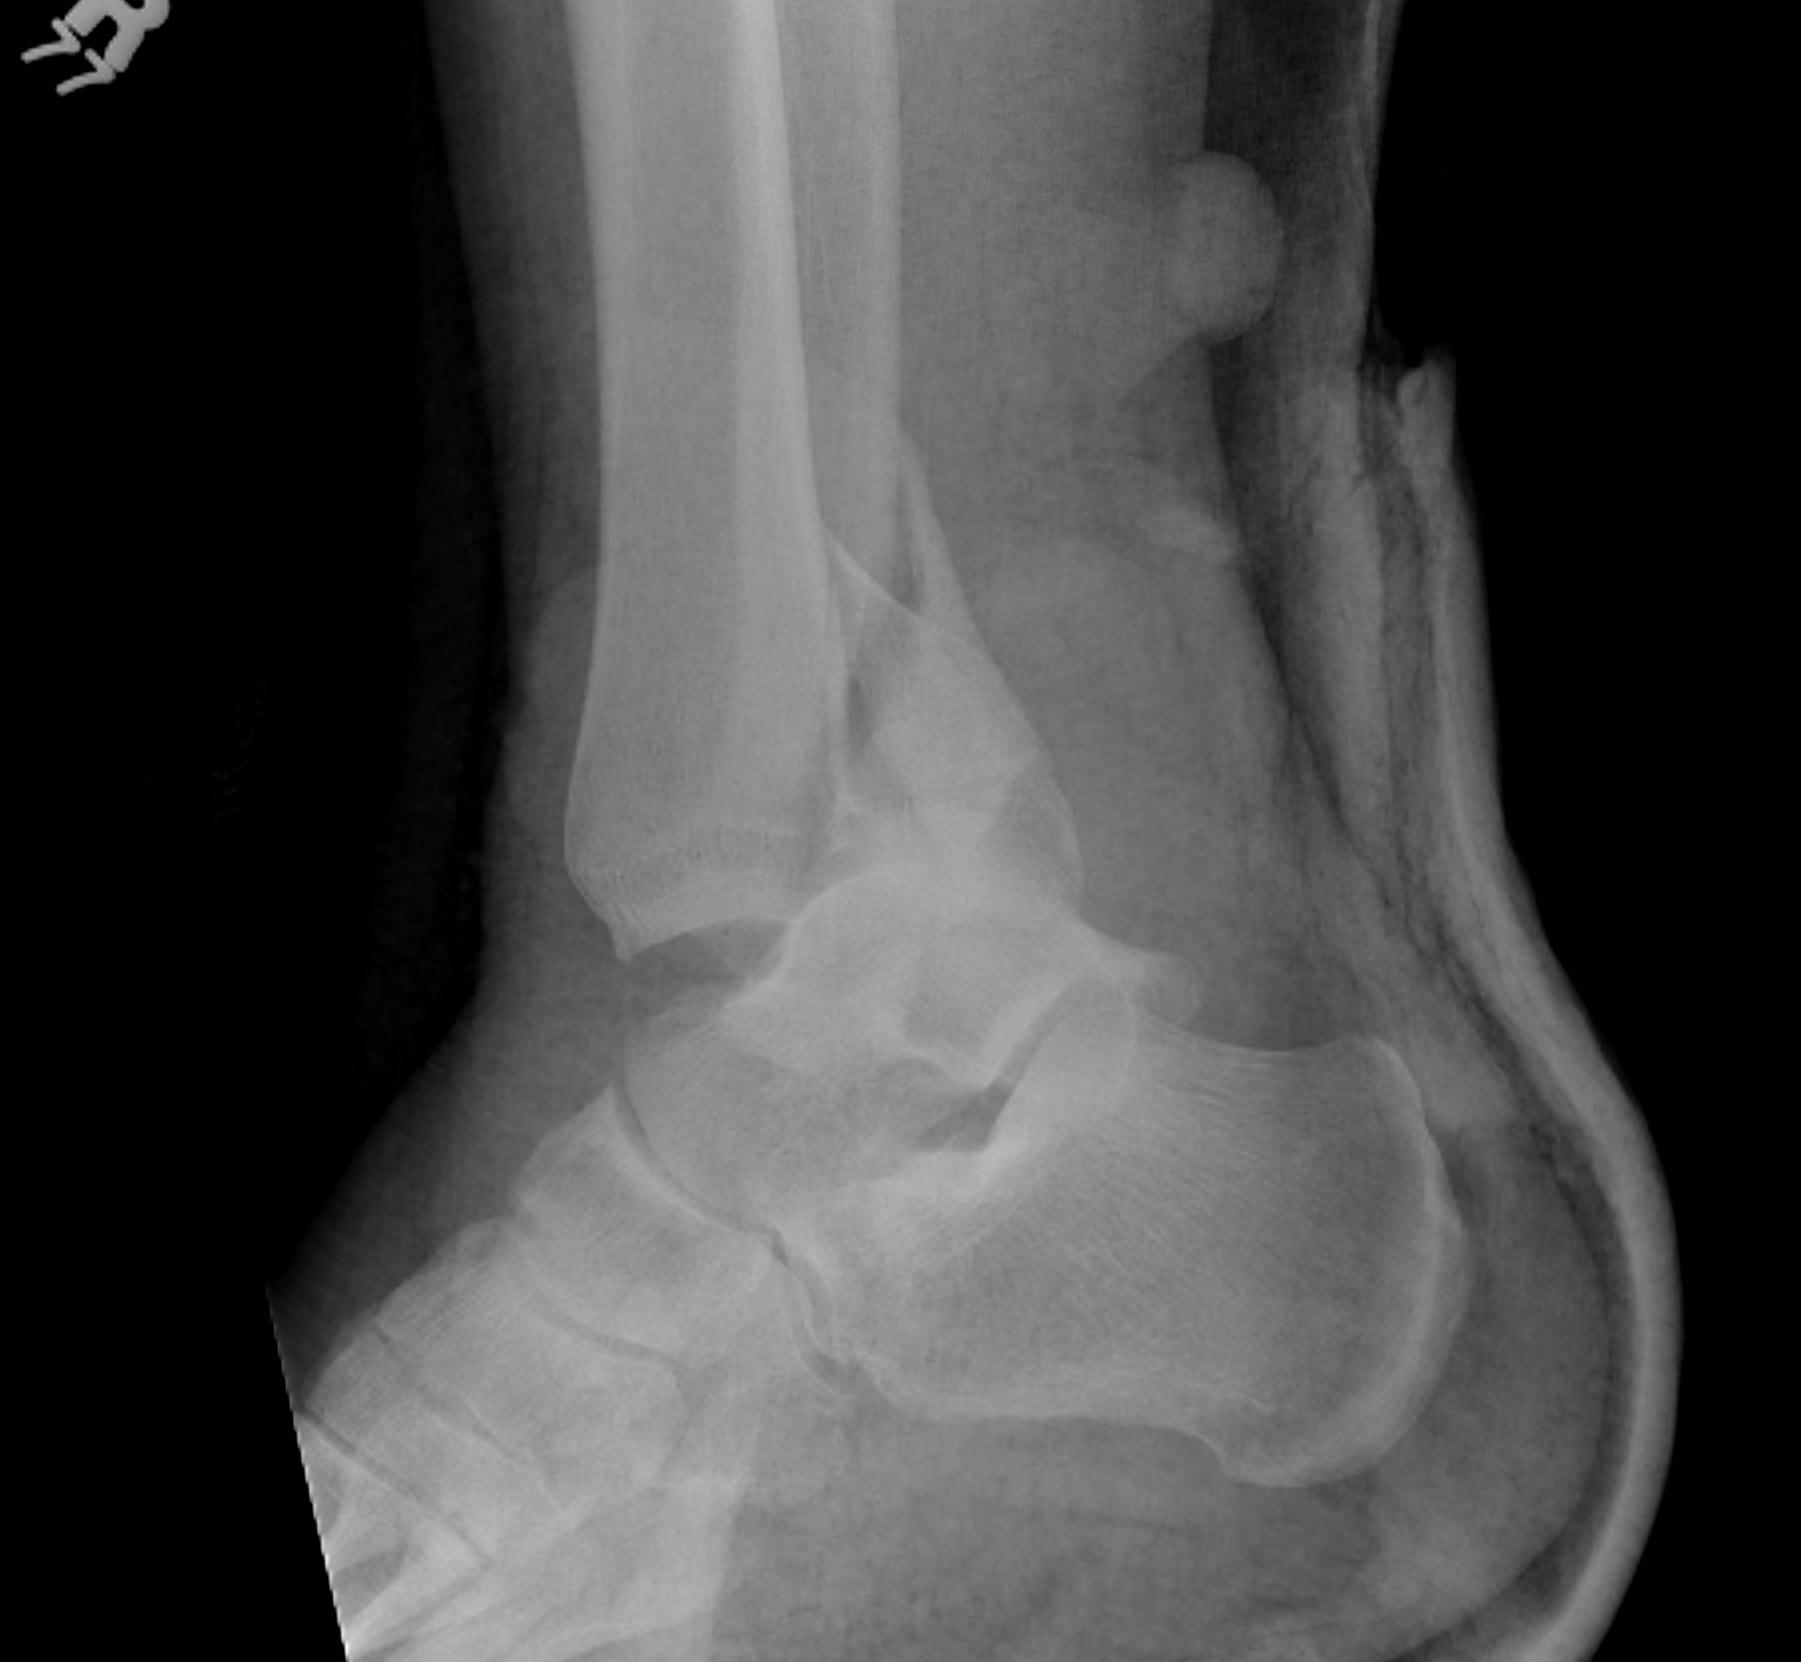

Dislocated ankle joint with large posterior malleolus

Articular incongruency

Posterior malleolus and syndesmotic injury